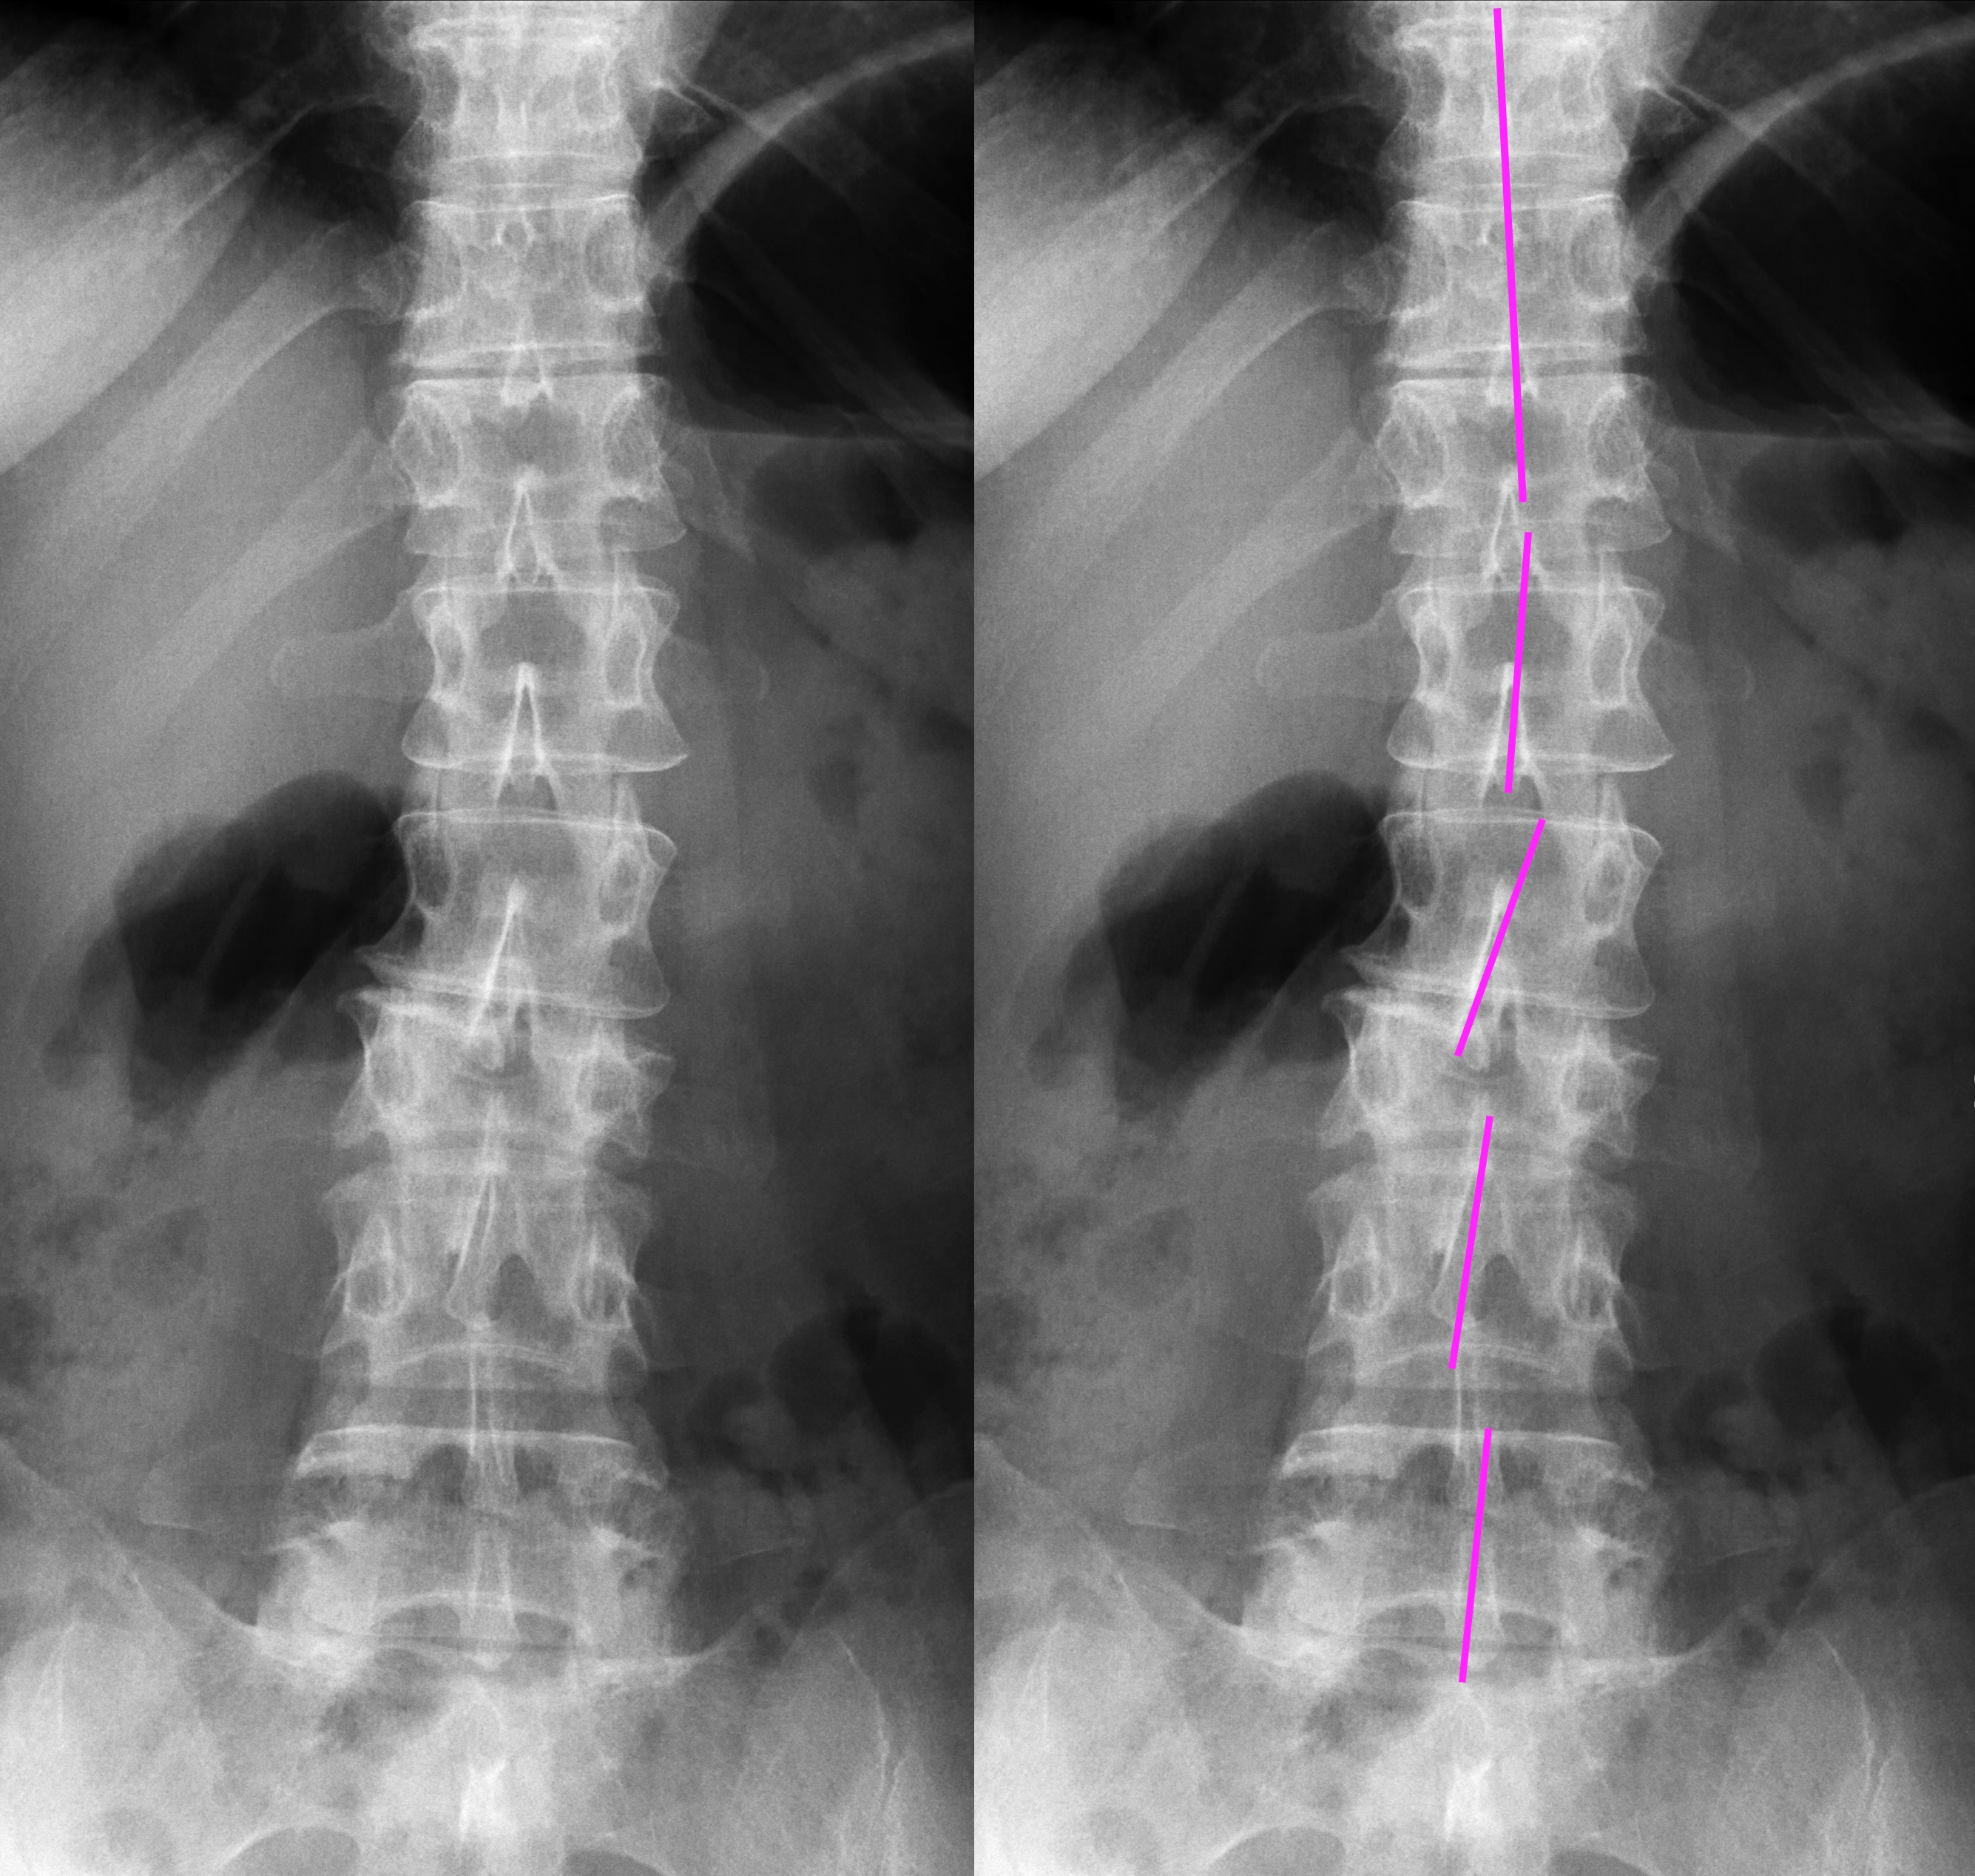

I've broken two of my vertebrae, it's compressing my spinal cord, I have a broken foot, and several broken teeth. It began a cascade of health issues I've dealt with ever since. However, this year, I finally found the right neurosurgeon capable of repairing my broken back. July 11, at UNM Hospital in Albuquerque, I am finally getting the surgery I've waited so long to get. It's a long recovery, but the first few months are going to be the toughest.